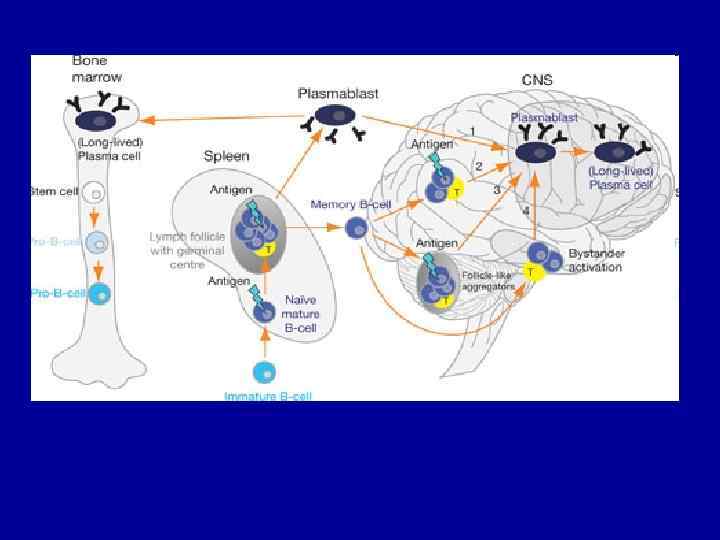

Figure 1. The paradigm for the role of B-cells in MS • Taken from Meinl E et al. B lineage cells in the inflammatory central nervous system environment: migration, maintenance, local antibody production, and therapeutic modulation. Ann Neurol 2006; 59: 880 -892. Reproduced with permission from John Wiley & Sons Ltd.

B-cells are directly linked to the pathogenesis of MS • B-cells are directly linked to the pathogenesis of • • MS Plasma cells and B-cells are commonly found in B-cell lesions 19 -21 and in all phenotypes of MS 22 More recently, B-cell follicles have been identified in the brain meninges of patients with secondary-progressive MS, linked to cortical lesion formation 23, 24 B-cells have also been identified in the CSF of patients with MS 25, 26 B-cells in CNS may be predictive of disease progression 26